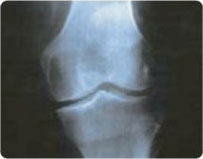

STAGE 2

Absent Joint Space